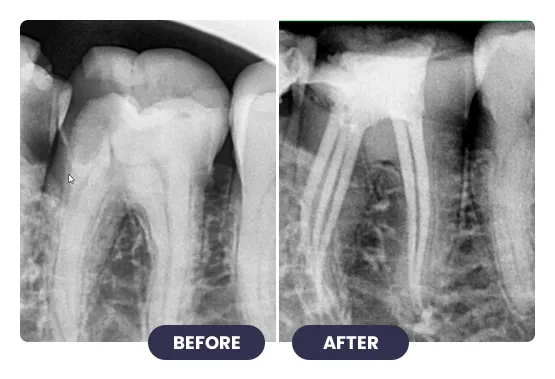

Treating infected or damaged teeth with root canal treatment at iCube Dental is a precise, technique-sensitive procedure that requires professional expertise and careful planning.

Advanced tools and methods are used to remove infection, clean the tooth canals, and restore tooth structure. This treatment relieves pain, prevents further infection, and preserves your natural tooth, ensuring proper bite and chewing function.